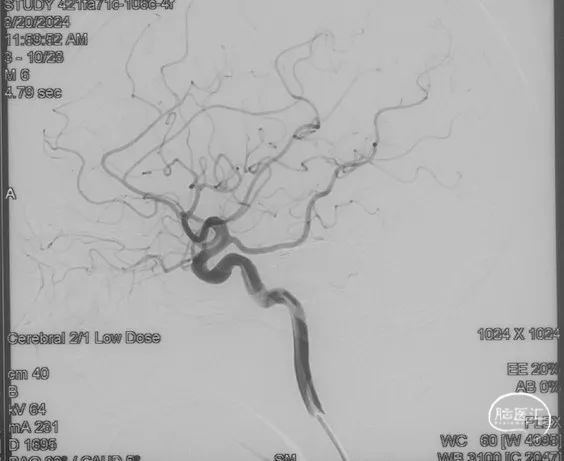

术前造影

证实为TDAVF,为岩上窦型。R-ECA正侧位见右侧脑膜中动脉分支、枕动脉分支、颞浅动脉分支向瘘口供血,经幕上迂曲扩张的静脉、中脑周围静脉、基底静脉向深部静脉引流。

R-ICA正侧位见右侧脑膜垂体干向瘘口供血

L-ICA正侧位见左侧脑膜垂体干分支向瘘口供血

L-ECA正侧位未见向瘘口供血

L-VA、R-VA正侧位右侧小脑上动脉脑膜支向瘘口供血

选取工作角度,正侧位造影